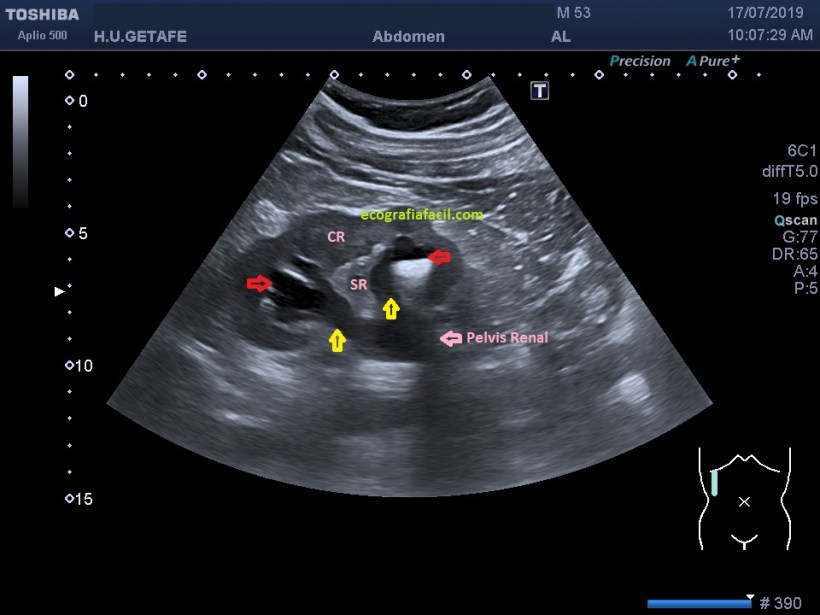

La uropatía obstructiva puede provocar una hidronefrosis que podemos confundir con un seno renal poliquístico, pero es importante buscar las interconexiones que tienen los cálices renales que son confluyentes todos en la pelvis renal, poder demostrar dicha confluencia puede ser una dato que permita a la radióloga emitir un informe en este sentido.

La manera de demostrar esto es buscando angulaciones con la sonda y movilización del paciente hasta conseguir una imagen como esta:

1

Si conseguimos demostrar la confluencia de los pielones caliciales y seguir el uréter, habremos demostrado la dilatación del sistema calicial (imagen1).